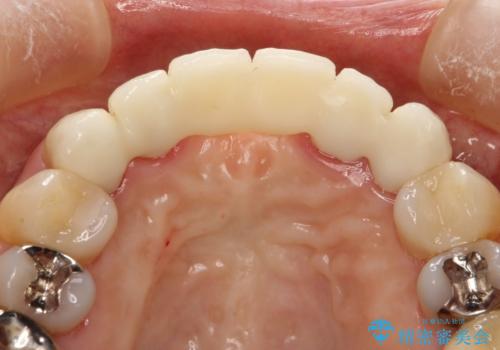

前歯のブリッジの見栄えが悪い→見えないところからしっかりとやり直しを

一見きれいにはいっているセラミックも、はずして中の状態をみるとひどいことが多い。これは、中の土台の状態や処理のクオリティは、短期的には問題を起こしづらく、患者さんには見えない部分だからです。

かぶせ物の種類:PFZ standard